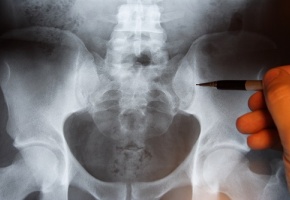

Une proportion importante des fractures survient chez les sujets de moins de 70 ans ou chez les sujets non ostéoporotiques, ce qui suggère que traiter seulement les sujets ayant une ostéoporose ne permettra pas de réduire le nombre de fractures en population générale.

Depuis des décennies, on sait qu’une densité minérale osseuse basse est le facteur prédictif de fracture le plus robuste et le plus reproductible. Cependant, la majorité des fractures surviennent chez les patients n’ayant pas d’ostéoporose. On préfère donc maintenant définir une population à risque de fractures non ostéoporotiques. Afin de mieux connaître la répartition des sujets ayant fait une fracture entre ceux qui ont ou non une ostéoporose et en fonction de l’âge, une étude de cohorte de population australienne a été mise en place, 3700 participants âgés de plus de 50 ans ont participé à l’étude. Les fractures après traumatisme minime étaient prouvées par des radiographies et la mortalité était définie à partir de registres nationaux. Tous les participants de cette étude épidémiologique, la « Dubbo Osteoporosis Epidemiology Study », avaient également une ostéodensitométrie. Globalement, 21 % des femmes et 11 % des hommes avaient une ostéoporose à l’ostéodensitométrie. En analyse uni-variée, 21 % des fractures totales chez les femmes et 16 % des fractures totales chez les hommes étaient attribuables à l’ostéoporose. Une ostéoporose combinée à un âge avancé (> 70 ans) expliquait 34 % des fractures chez les femmes et 35 % des fractures chez les hommes. Toutefois, ces deux facteurs n’expliquaient que 60 % des fractures de hanche. Environ 99 % de la mortalité après fracture chez les femmes et 66 % de la mortalité après fracture chez les hommes était attribuable à l’âge avancé, à l’ostéoporose et aux fractures. Toutefois, c’était surtout l’âge avancé qui représentait le facteur attribuable le plus important. En conclusion, une proportion importante des fractures survient chez les sujets de moins de 70 ans ou chez les sujets non ostéoporotiques, ce qui suggère que le seul traitement des sujets ayant une ostéoporose ne réduira pas de manière importante le nombre de fractures dans la population générale. Reste maintenant à mieux comprendre les facteurs de risque de fracture en dehors de l’ostéoporose et de l’âge !